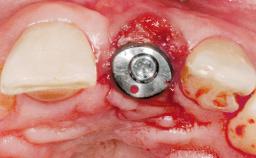

Late Placement of an Implant in a Maxillary Left Central Incisor Site

Bone Augmentation Horizontal|Staged

Augmentation Materials Xenogenous|Membrane

Bone Volume Deficient horizontally, requiring prior grafting